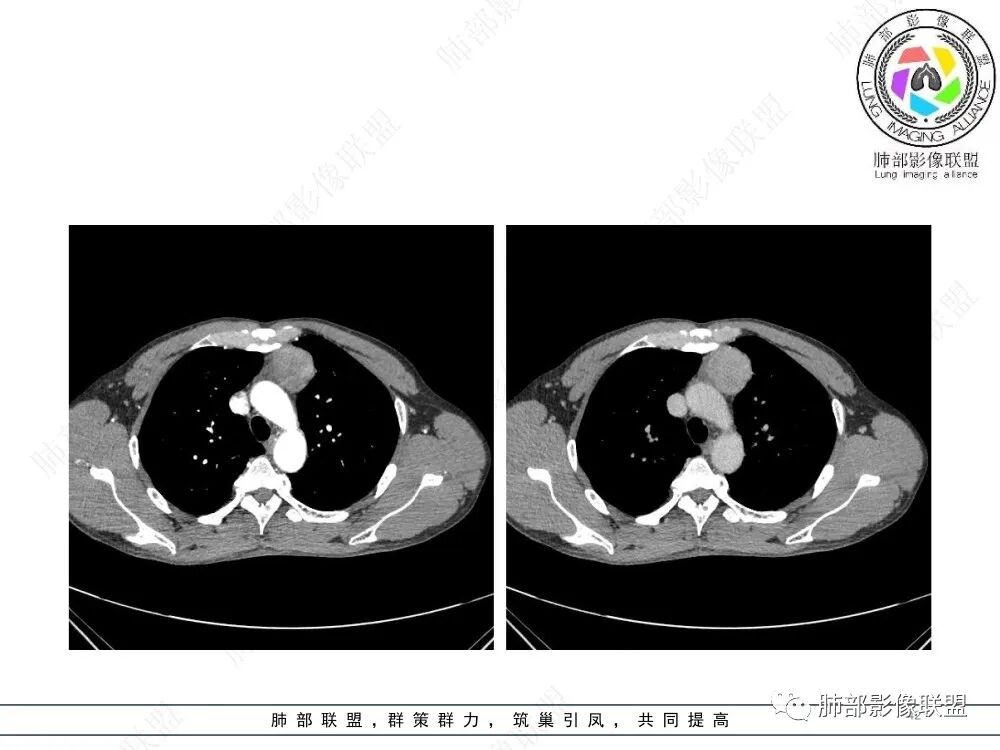

放射小白:男性47岁,前纵隔团块状占位,边界尚清,增强中度强化,内部疑似纤维分隔,常规考虑胸腺瘤可能(A/AB型),鉴别类癌、CD。

瑞欣:中年男性,检验未见明显异常,前纵隔软组织快影,边界清,可见明显强化,首先考虑胸腺瘤,鉴别淋巴瘤,畸胎瘤,生殖细胞瘤。

金豆:晨读:定位前纵隔,膨胀性生长,质地中等,边界清,有浅分叶,中等强化,似乎有裂隙低密度,常规胸腺瘤(B1)。

Yishion:晨读:纵隔占位,偏侧生长,边界清楚,有浅分叶,强化明显,其内似见纤维分隔,常规考虑胸腺瘤(AB型)。

蓝天白云:晨读:47岁男,前纵隔占位,边界清,有浅分叶,中等强化,胸腺瘤(B1)。

宇宙:前纵膈偏左类圆形肿块,边界清晰光整,与大血管脂肪间隙清,密度均匀,轻中度强化,考虑胸腺瘤,A型?鉴别胸腺癌。

玫:男,47岁,咳嗽,咳痰一年,前纵隔软组织密度肿块影,边界清晰,内密度均匀,增强扫描轻度强化,考虑胸腺瘤可能。

周太狼:中年男性,前上纵隔胸腺区软组织团块占位,边界清,增强中度强化,内密度较均匀,常规考虑胸腺瘤。

月亮圆了!:前纵隔包块,边界清,有分叶,密度不均,中等强化,考虑胸腺瘤。

衡妈🇨🇳:中年男性,前纵隔偏左侧实性占位,密度相对均匀,边缘分叶,周围脂肪结构略模糊,增强后动脉期不均匀强化,有低密度区,纤维分隔显示不清。考虑胸腺瘤B1 B2型。

朱伟超:中年男性,前纵膈偏离中线肿块,浅分叶,内有分隔,中等不均匀强化,常规胸腺瘤。

流心明智:男,47,咳嗽、咳痰1年余。胸部CT:前纵膈偏左类圆形肿块,瘤肺界面清晰光整,纵隔侧部分层面絮状影?平扫密度较均匀,增强后轻度强化,内可见宽带及线样低密度分隔。邻近左上肺受压凹陷。考虑胸腺肿瘤,AB型?胸腺Ca?鉴别淋巴瘤、N源性肿瘤、CD等。

2、影像特点:前纵隔偏左侧软组织影,密度相对均匀,未见明显包膜钙化及实质内钙化,局部边缘浅分叶,周围脂肪间隙密度增高、浑浊,未见侵犯大血管、未见纵隔内淋巴结转移、未见侵犯心包内结构、未见胸膜转移结节、未见肿块沿着纵隔胸膜蔓延,未见胸腔积液。增强后动脉期不均匀强化,未见明显纤维分隔。